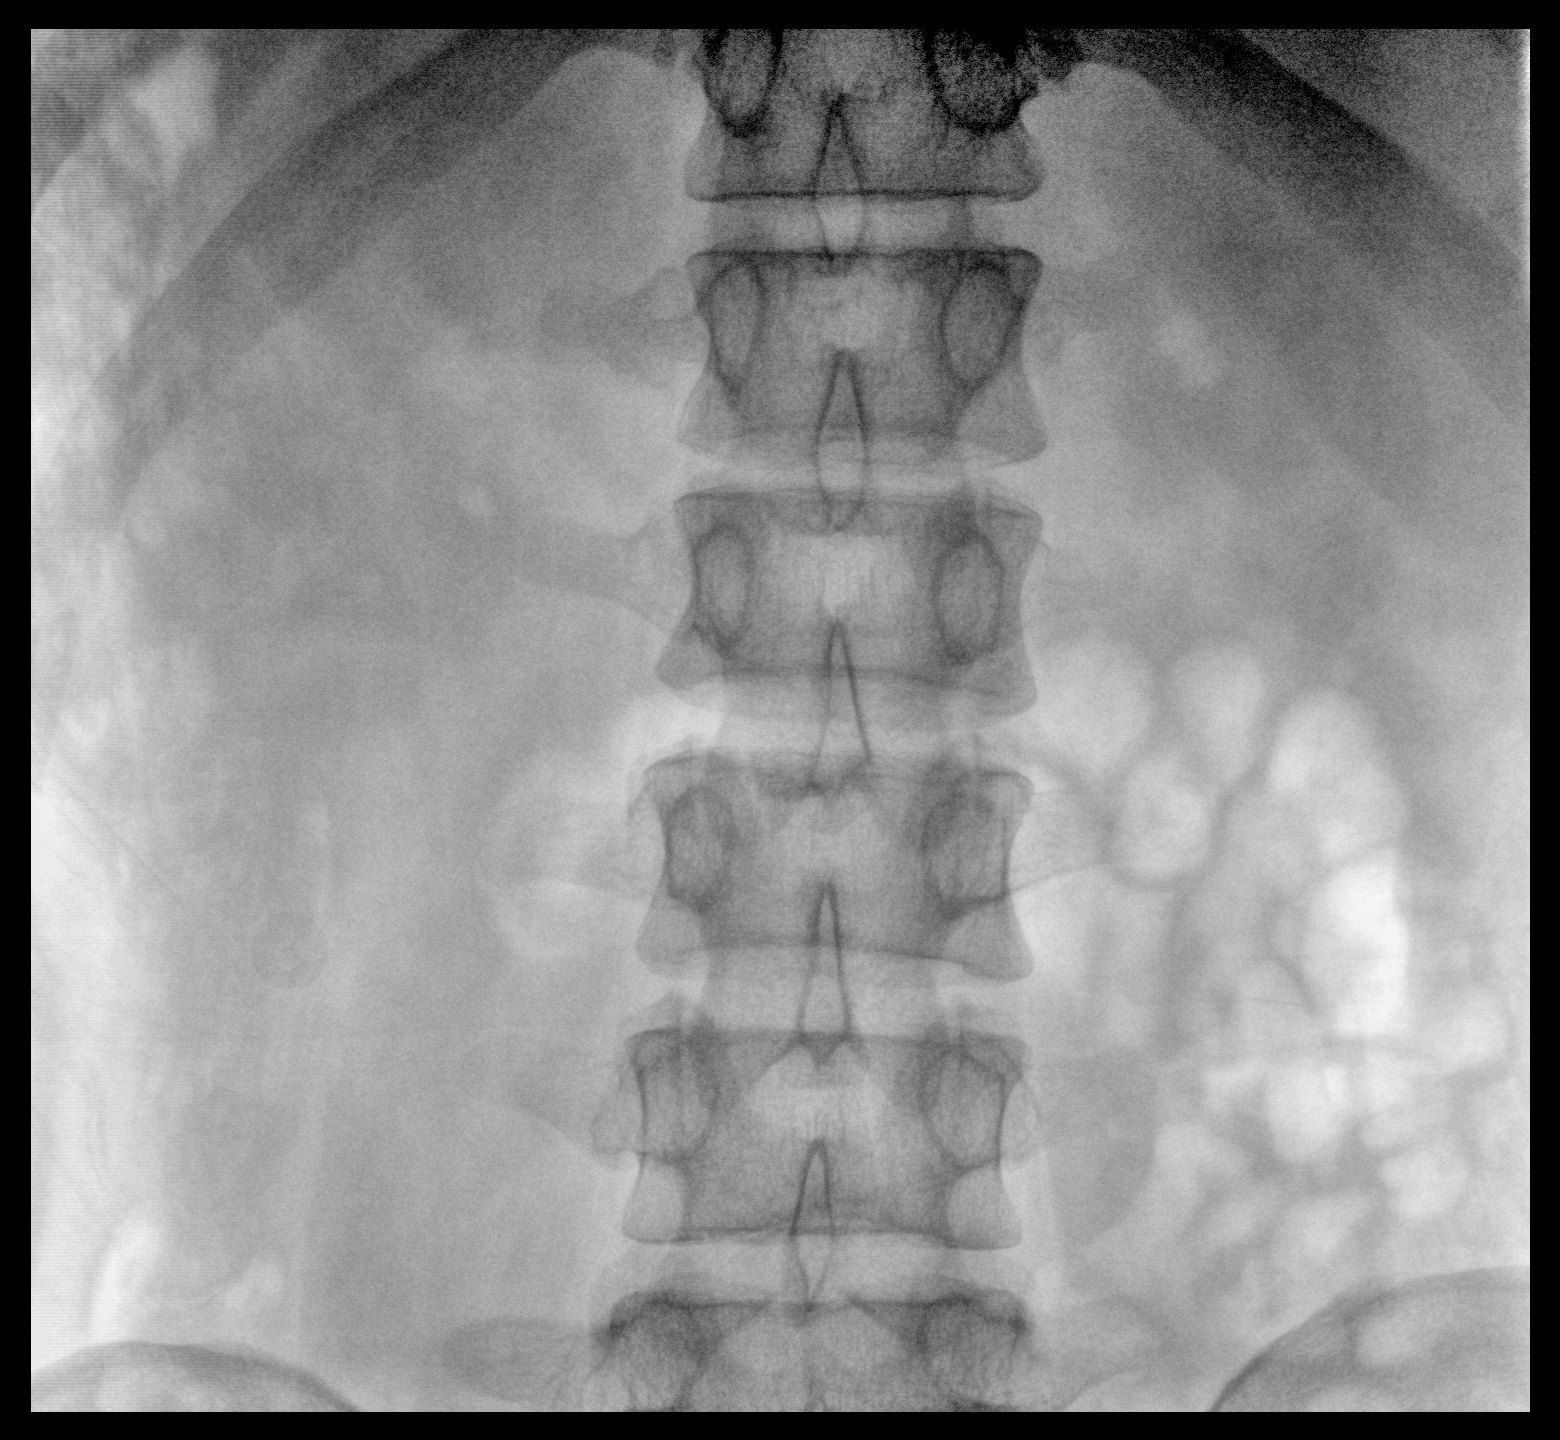

Clinical picture

臨床圖片